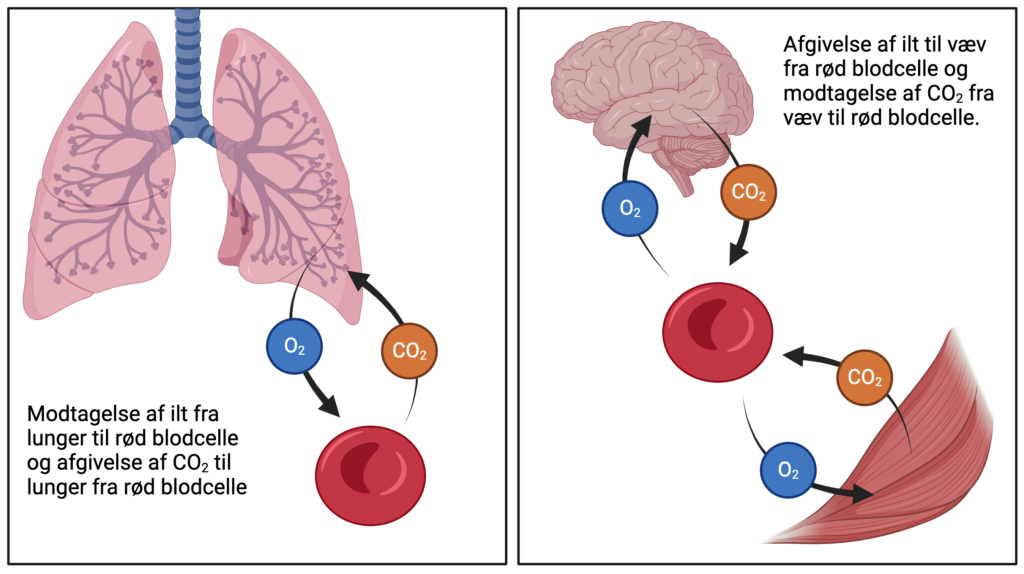

Røde blodceller har til opgave at transportere ilt rundt i kroppen. De modtager ilten i lungerne, hvorefter de transporterer det ud til kroppens væv. I vævet afgiver de ilten og optager herefter CO2, der transporteres tilbage til lungerne for at blive udåndet. Figur 1 illustrerer denne proces.